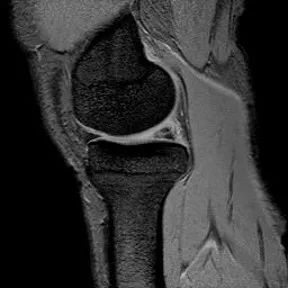

半月板桶柄状撕裂

1、多为纵形撕裂的特殊形式,有时来源于垂直(纵行)和水平撕裂2、多见于严重外伤的年轻患者3、内侧半月板发生率是外侧半月板的3倍

桶柄状撕裂MRI表现

1、宽度减小,在通过半月板体部的冠状面上蝶形消失,同时可见内移的半月板位于髁间窝、交叉韧带旁2、矢状面示残余的前角或后角变小或截断3、半月板前(后)角增宽或双半月板前(后)角征4、双前交叉韧带或双后交叉韧带征

桶柄状撕裂:宽度减小,在通过半月板体部的冠状面上蝶形消失,同时可见内移的半月板位于髁间窝、交叉韧带旁

桶柄状撕裂:半月板后角增宽

半月板撕裂:桶柄状撕裂(双前角征)

桶柄状撕裂(双后交叉韧带征)

桶柄状撕裂:双前交叉韧带征